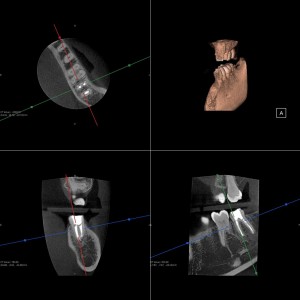

レントゲンを見ると根尖部に膿が溜まった様な黒い影が見えます。

これは歯の中の細菌によって根尖部に炎症が起きて症状が治らなかったと思います。

根の先までファイルが届いていない事がレントゲン上で観察されます。

ファイルを根尖まで届かせ根管内を洗浄・消毒し根管内を緊密に充填しました。

上のCT画像は拡大してご覧下さい。